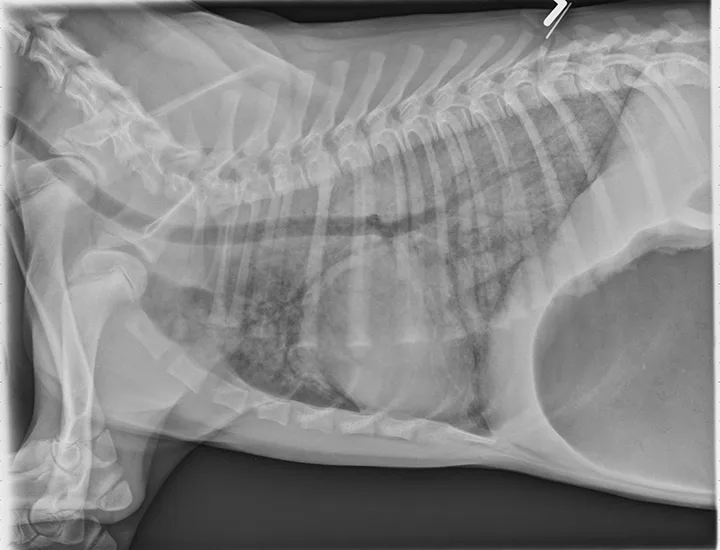

Thoracic radiographs can appear normal initially, but changes to the pulmonary parenchyma may become more apparent within 24 to 72 hours as respiratory injury progresses. Evidence of patchy pulmonary edema with bronchial, interstitial, or alveolar patterns may be observed [Figures 1 and 2].6,13,16,19 Right middle lung lobe consolidation and pleural effusion in cats have been reported.6,13,16 An alveolar pattern may be seen on serial radiographs in patients that develop secondary bacterial pneumonia.6

VD thoracic x-ray of dog showing opacity of lung parenchyma concentrated in caudal fields and overlapping cardiac silhouette.

FIGURE 2

A severe, patchy interstitial-to-alveolar pattern, more severe in the left hemithorax and caudodorsal lung fields, in a dog with smoke inhalation injury after a house fire